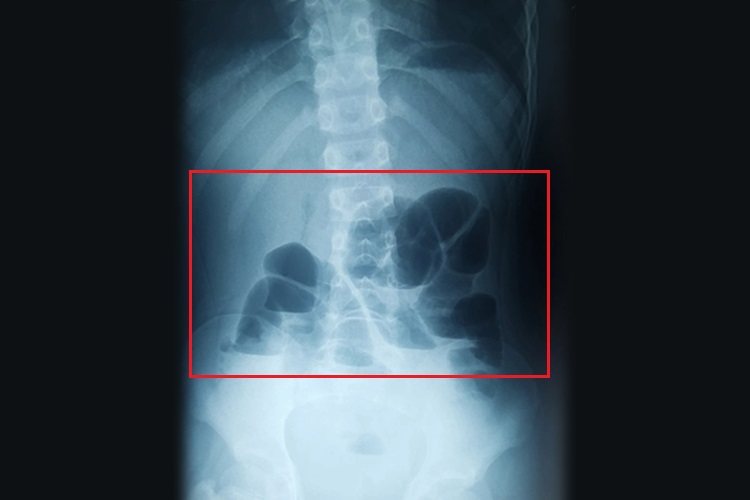

单纯性小肠梗阻表现为梗阻以上肠腔扩大积气积液,立位或水平侧位可见气液平面,梗阻以下肠腔萎陷无气或仅见少量气体。存在阶梯状液面征,在立位腹部平片上表现为梗阻近侧的肠曲胀气扩张,呈弓形或拱门状或倒U形,弓形肠曲两端的液面可处于不同高度,多个弓形肠曲液面在腹部自左向右下平行排列成阶梯状。